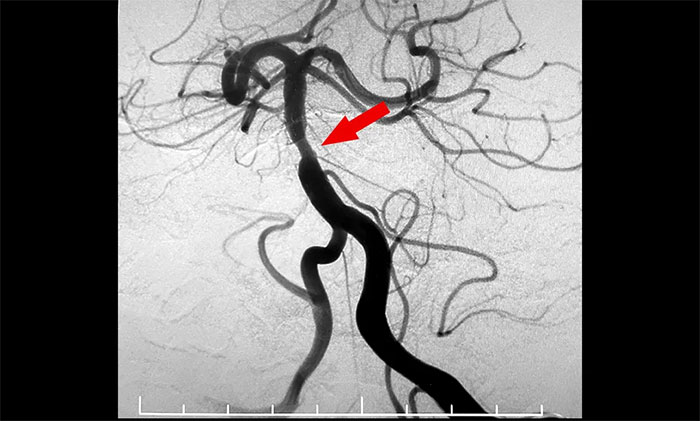

7月29日,经过充分的准备工作,席刚明教授、王贵平博士在介入团队协助下顺利为患者实施了手术。术中凶险的就是球囊扩张狭窄,如果掌握不好扩张球囊的位置和扩张速度,势必造成更复杂的血管夹层甚至出血。历时两个多小时奋战,席刚明教授、王贵平博士凭借丰富的经验及精准的手法顺利地于基底动脉狭窄处进行了球囊扩张,并顺利置入支架,造影可见左侧椎动脉、基底动脉、双侧大脑后动脉、双侧小脑上动脉、左侧小脑前下动脉显影可,基底动脉狭窄明显改善。最终,患者基底动脉得以顺利开通,手术获得圆满成功,打开了患者的“生命通道”。

▲ 基底动脉顺利开通